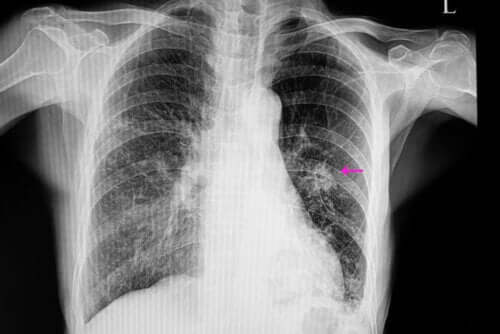

Dans ces cas, les nodules ont généralement un aspect irrégulier sur la radiographie, avec des bords mal définis. Par ailleurs, ils sont généralement plus petits que les nodules bénins et sont associés à certains facteurs de risque tels que :

Une fois que cela est clair, il est nécessaire de réaliser quelques tests d’imagerie pour localiser le nodule. Par ailleurs, les images permettent d’observer certaines caractéristiques comme la forme et la taille. Ces aspects sont fondamentaux pour distinguer un nodule bénin d’un nodule éventuellement malin.

Les plus utilisées sont la radiographie du thorax et le scanner. Afin de connaître la cause exacte du nodule pulmonaire, on effectue parfois des biopsies qui permettent d’analyser le tissu qui le forme.